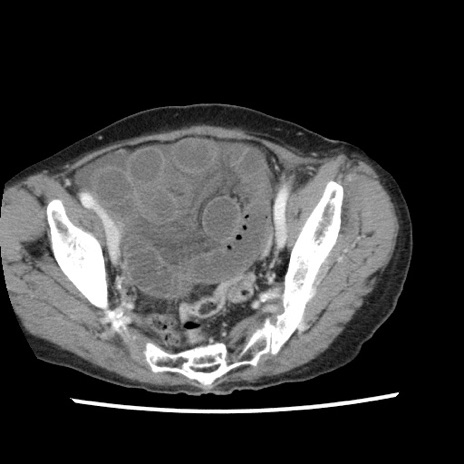

症例1(横断像)

【症例】80歳代女性

【主訴】腹痛

【現病歴】8時間前から腹痛あり来院。

【既往歴】糖尿病、脂質異常症、子宮体癌にて子宮全摘術

【身体所見】意識清明・会話良好だが腹痛で苦悶様、全腹部にわたって反跳痛と圧痛あり

【データ】WBC 13600、CRP 0.14、LDH 224、CK 90